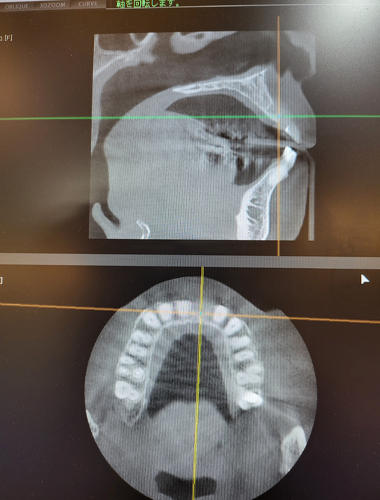

歯科用CTのデータを元に行うシムプラントガイドシステム

当院では、歯科用CTを導入しております。歯科用CTは、3次元の立体画像を得る事ができるので、より多くの情報を得る事ができます。シムプラントガイドシステムとは、この歯科用CTで撮影したデータを取り込み、診断から顎の骨に穴を明けるドリリングやインプラント埋入まで正確にガイドする事ができます。